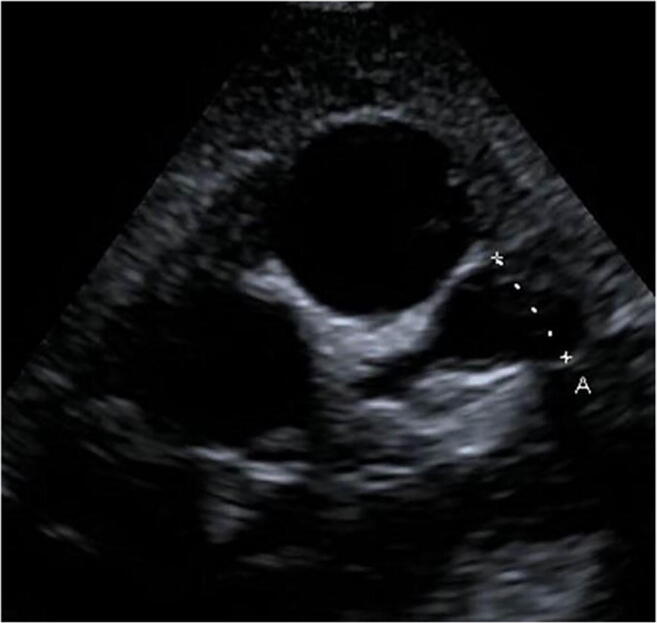

Of all patients, seven patients seemed to have a segmental dilation of the coronary arteries in echocardiography (Fig. 2). These findings were confirmed in a cardiac angiography during follow up.

Fig. 2.

Transthoracic echocardiography, parasternal short-axis view. Giant aneurysm (A = 10 mm) of the LAD in a 3-year-old girl with Kawasaki disease